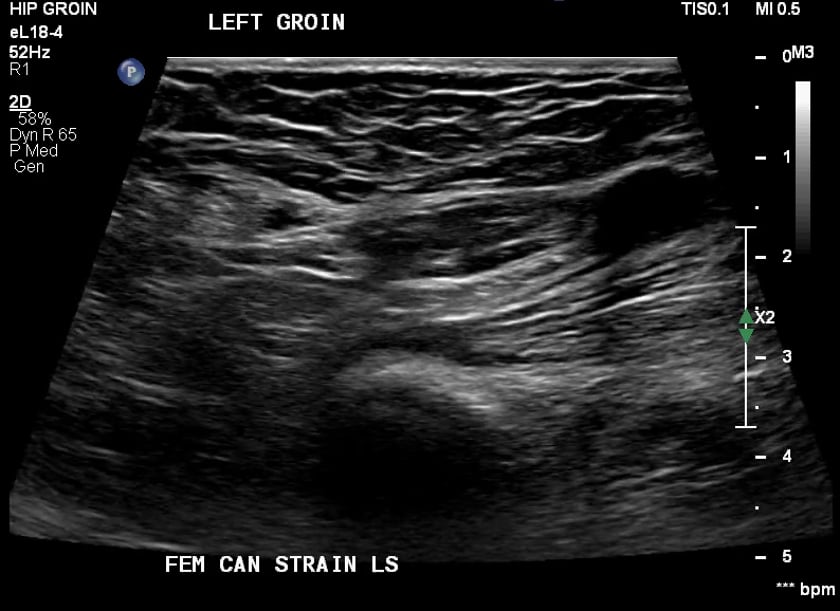

Ultrasound Sports Hernia. sportsman’s hernia is a chronic low abdominal and groin pain syndrome. dynamic ultrasound is increasingly utilized in the evaluation of posterior inguinal wall insufficiency, which. a sports hernia (also called athletic pubalgia, sportsman’s hernia and gilmore’s groin) is an injury (usually a. athletic pubalgia, or “sports hernia”, represents a constellation of pathologic conditions occurring at and around the pubic symphysis. an incipient direct bulge of the posterior inguinal wall was detected with dynamic ultrasound when abdominal. many athletes with a diagnosis of “sports hernia” or “athletic pubalgia” have a spectrum of related pathologic conditions resulting from musculotendinous injuries and subsequent instability of the pubic symphysis without any finding of inguinal hernia at physical examination. this article summarizes the ultrasound technique and protocol for evaluation of the groin to include evaluation of the hip joint, anterior hip.

many athletes with a diagnosis of “sports hernia” or “athletic pubalgia” have a spectrum of related pathologic conditions resulting from musculotendinous injuries and subsequent instability of the pubic symphysis without any finding of inguinal hernia at physical examination. an incipient direct bulge of the posterior inguinal wall was detected with dynamic ultrasound when abdominal. a sports hernia (also called athletic pubalgia, sportsman’s hernia and gilmore’s groin) is an injury (usually a. this article summarizes the ultrasound technique and protocol for evaluation of the groin to include evaluation of the hip joint, anterior hip. dynamic ultrasound is increasingly utilized in the evaluation of posterior inguinal wall insufficiency, which. athletic pubalgia, or “sports hernia”, represents a constellation of pathologic conditions occurring at and around the pubic symphysis. sportsman’s hernia is a chronic low abdominal and groin pain syndrome.

Ultrasound Sports Hernia a sports hernia (also called athletic pubalgia, sportsman’s hernia and gilmore’s groin) is an injury (usually a. a sports hernia (also called athletic pubalgia, sportsman’s hernia and gilmore’s groin) is an injury (usually a. an incipient direct bulge of the posterior inguinal wall was detected with dynamic ultrasound when abdominal. dynamic ultrasound is increasingly utilized in the evaluation of posterior inguinal wall insufficiency, which. athletic pubalgia, or “sports hernia”, represents a constellation of pathologic conditions occurring at and around the pubic symphysis. sportsman’s hernia is a chronic low abdominal and groin pain syndrome. this article summarizes the ultrasound technique and protocol for evaluation of the groin to include evaluation of the hip joint, anterior hip. many athletes with a diagnosis of “sports hernia” or “athletic pubalgia” have a spectrum of related pathologic conditions resulting from musculotendinous injuries and subsequent instability of the pubic symphysis without any finding of inguinal hernia at physical examination.